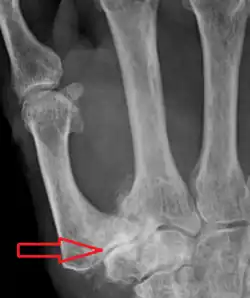

Diagnosis

TMC OA is diagnosed based on symptoms and signs.[8] Radiographs can confirm the diagnosis and the severity of TMC OA. Other diagnoses in this region include scaphotrapezial trapezoid arthritis and first dorsal compartment tendinopathy (De Quervain syndrome) although these are usually easy to distinguish.

TMC OA severity was classified by Eaton and Littler which can be simplified as follows:[21][22]

Stage 1:

- slight widening of the joint space

- < 1/3 subluxation of the joint (in any projection)

Stage 2:

- Osteophytes, < 2 mm in diameter, are present. (usually adjacent to the volar or dorsal facets of the trapezium)

Stage 3:

- Osteophytes, > 2 mm in diameter, are present (usually adjacent to the volar and dorsal facets of the trapezium)

- Slight joint space narrowing

Stage 4:

- Narrow joint space

- Concomitant scaphotrapezial arthritis

A simpler classification is no arthritis, some arthritis, and severe arthritis.[23] This simpler classification system omits the potentially contradictory details of the Eaton/Littler classification and keeps scaphotrapezial arthrosis separate.